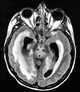

Meningoencephalitis

Meningoencephalitis (; from Greek μῆνιγξ meninx, "membrane", ἐγκέφαλος, enképhalos "brain", and the medical suffix -itis, "inflammation"), also known as herpes meningoencephalitis, is a medical condition that simultaneously resembles both meningitis, which is an infection or inflammation of the meninges, and encephalitis, which is an infection or inflammation of the brain. Signs and symptoms Signs of meningeoncephalitis include unusual behavior, personality changes, and thinking problems.Symptoms may include headache, fever, pain in neck movement, light sensitivity, and seizure. [Source: Wikipedia ]